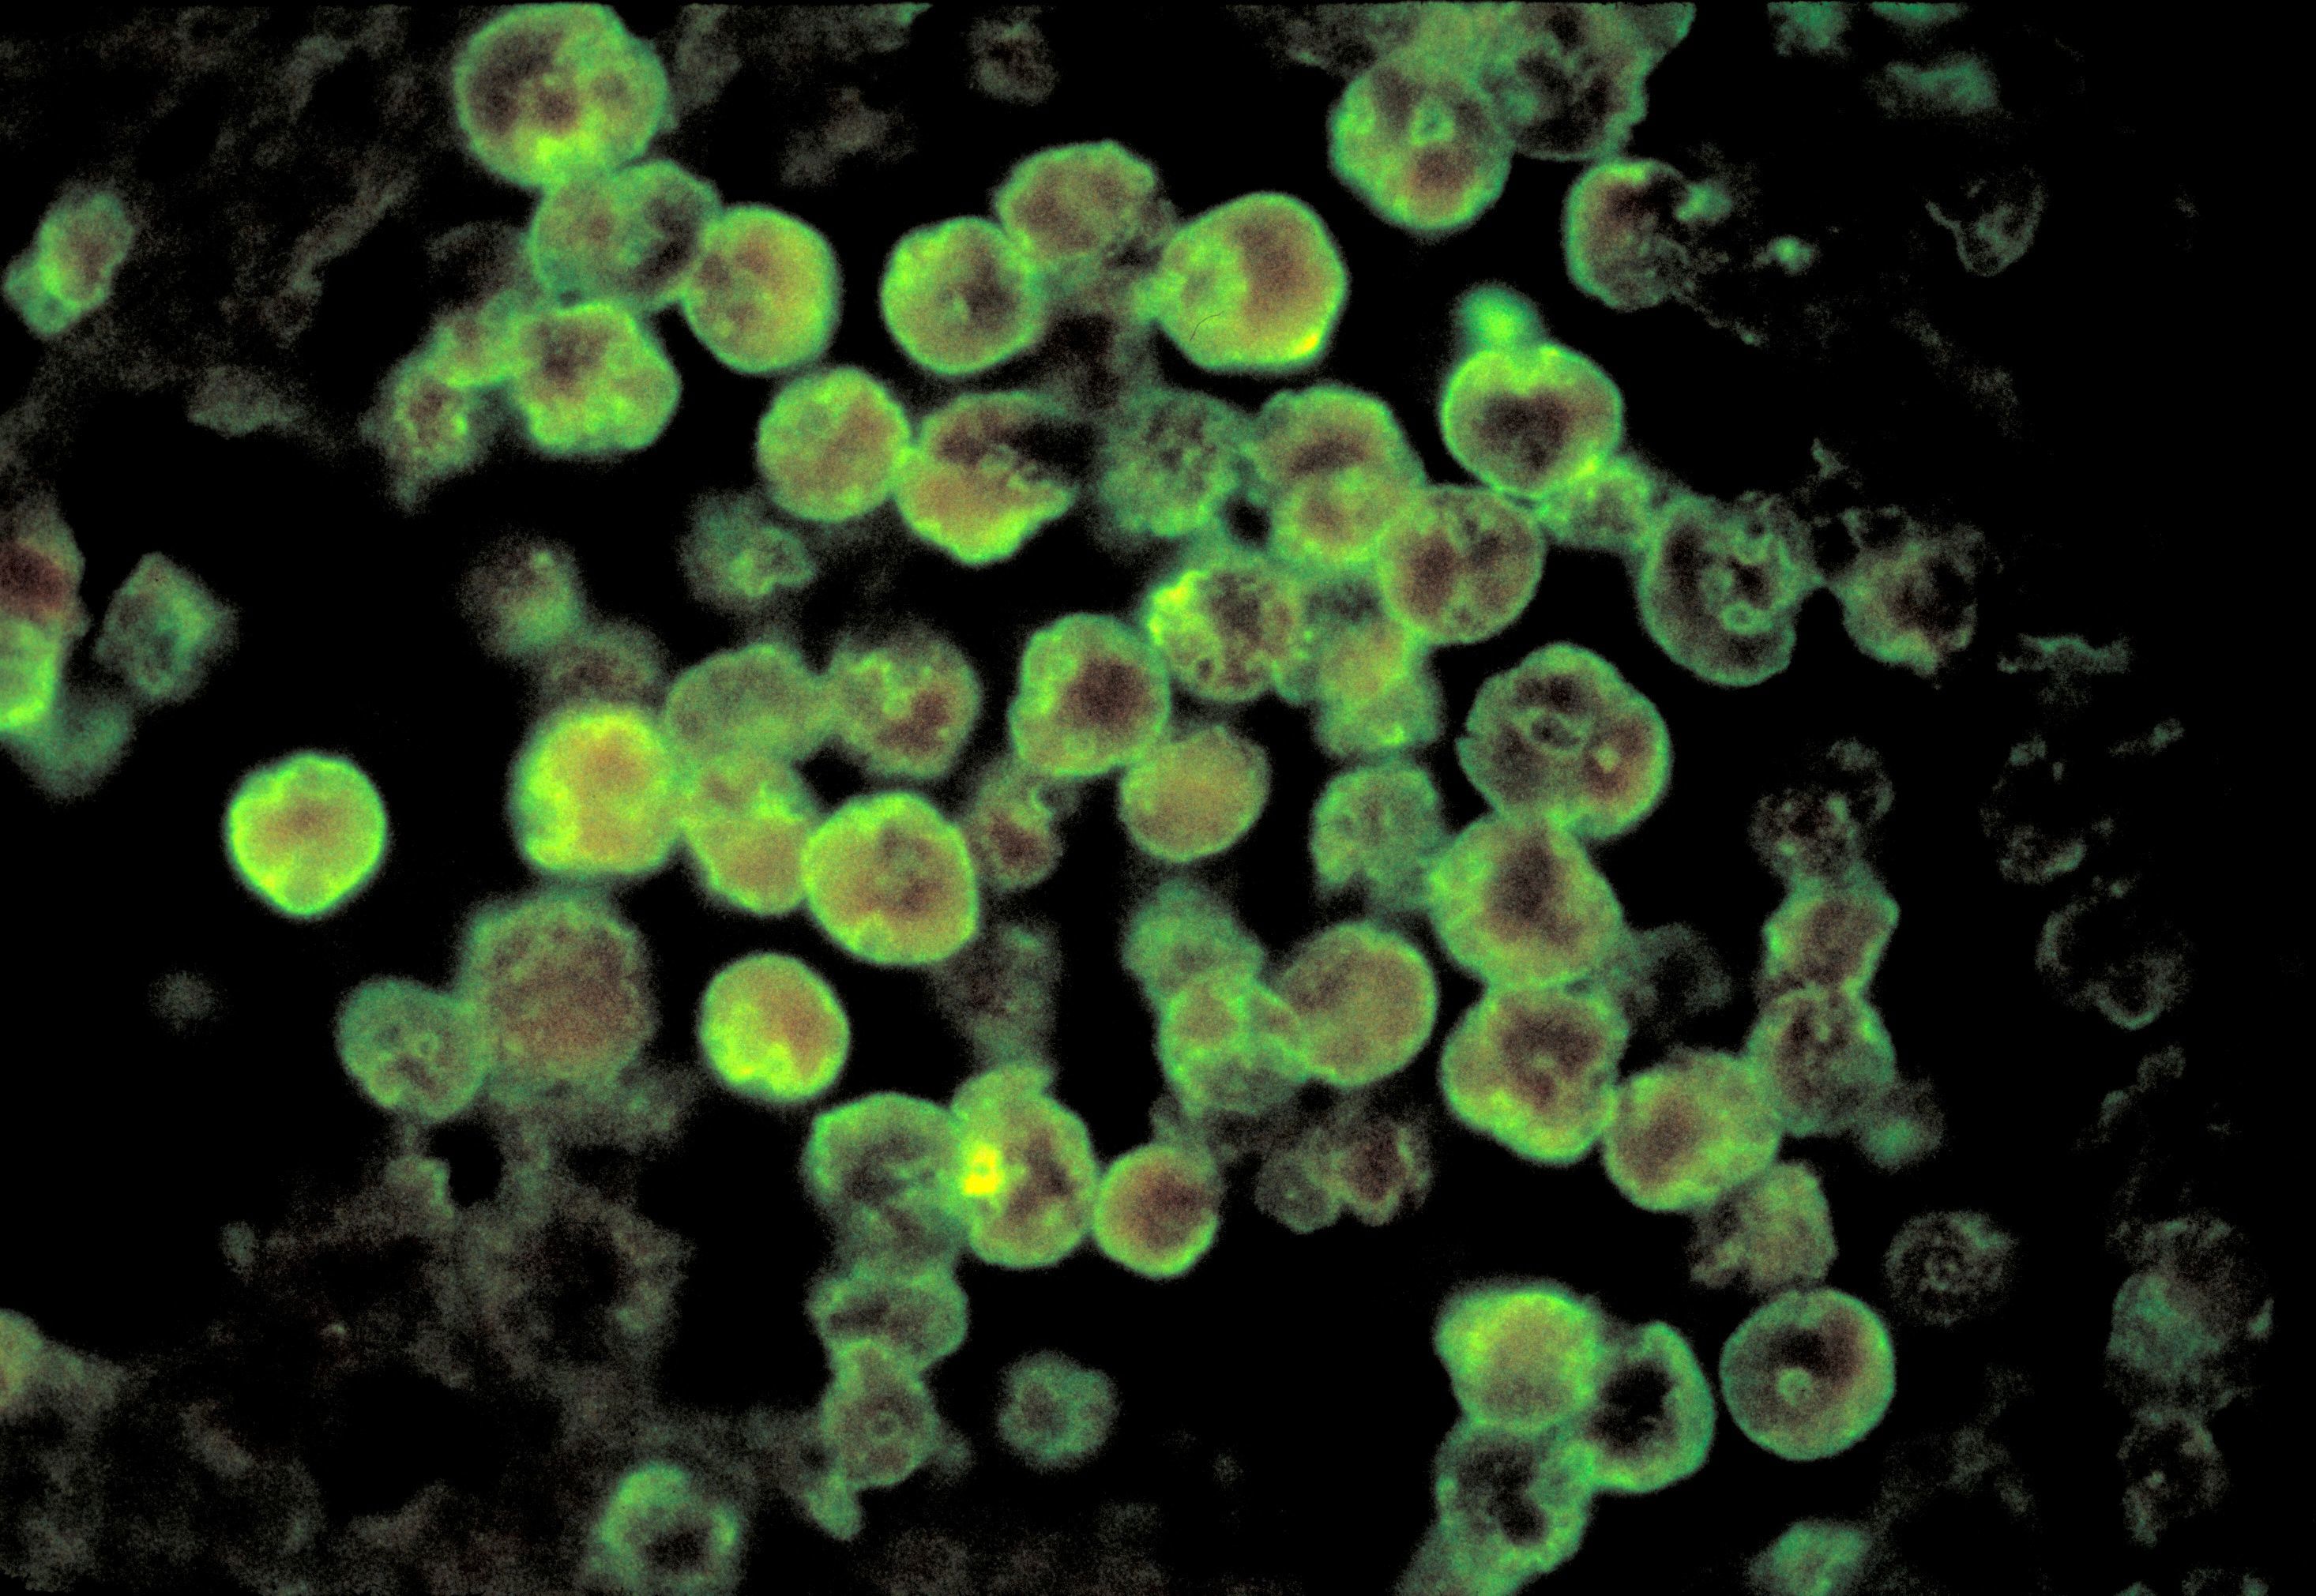

The victim died from Naegleria fowleri infection, which "destroys brain tissue, causing brain swelling and in certain cases, death," the Arkansas Department of Health said in a news release on Thursday.

Naegleria fowleri is an amoeba that lives in soil and warm freshwater lakes, rivers, ponds and hot springs. In rare instances, people have gotten Naegleria fowleri infections from recreational water that had an insufficient amount of chlorine in it, such as pools, splash pads or surf parks, according to the US Centres for Disease Control and Prevention.

This type of amoeba enters the body through the nose, most commonly when people go swimming, diving or put their heads underwater in freshwater bodies, according to the CDC.

The amoeba travels up to the brain, destroying brain tissue and causing an almost-always fatal infection called primary amebic meningoencephalitis (PAM).